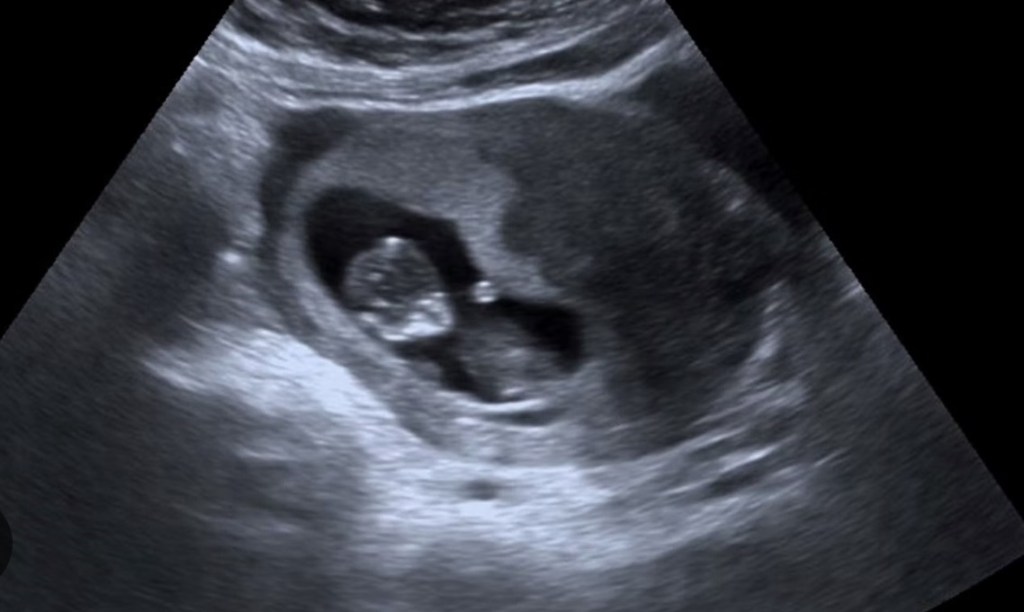

As the days pass, the nerves and disbelief begin to transform into a sense of anticipation and excitement. The reality of the pregnancy starts to sink in, and you begin to embrace the journey ahead.